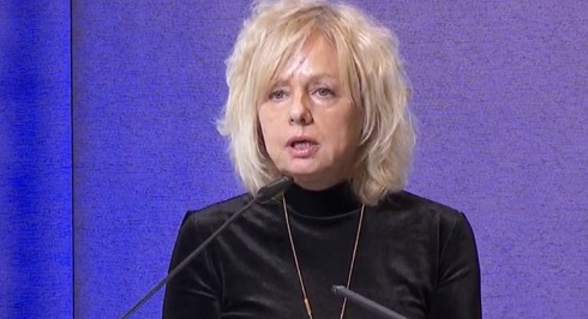

حذرت الدكتورة تاتيانا غولوفشانسكايا أخصائية أمراض الجهاز الهضمي من أن الاستخدام غير المنضبط لمسكنات الألم يشكل خطرا صحيا خفيا.

ووفقا لها، قد يؤدي العلاج الذاتي طويل الأمد بمضادات الالتهاب غير الستيرويدية إلى تشخيص طبي محدد- قرحة المعدة الناتجة عن مضادات الالتهاب غير الستيرويدية، التي تتطور عندما يتناول الشخص مسكنات الألم بانتظام - وغالبا ما يكون الإيبوبروفين - لعلاج الصداع النصفي أو آلام الأسنان أو الآلام المزمنة.

وتقول: "للوهلة الأولى، لا يبدو الأمر مثيرا للقلق، يتناول الشخص حبة دواء، ويخف الألم. ولكن تدريجيا، قد يتحول تناول الأدوية إلى عادة، حيث يبدأ الشخص في الاعتماد على مسكنات الألم بشكل منتظم".

ووفقا له، بمرور الوقت، يتفاعل الجسم مع هذا الإجهاد، وقد تكون العواقب وخيمة، بدءا من قرحة المعدة وصولا إلى نزيف في الجهاز الهضمي. ولا تكمن المشكلة في الدواء نفسه، بل في سوء استخدامه.

وتقول مؤكدة: "لكل دواء دواعي استعمال وموانع استخدام، بالإضافة إلى نظام جرعات دقيق، والالتزام به أمر مهم جدا. كما يجب أن نتذكر- أن الإيبوبروفين والباراسيتامول، خلافا للاعتقاد الشائع، ليسا آمنين تماما".

وتشير إلى أن تناولهما دون إشراف طبي، قد يكون لهما تأثير سام على الكبد. لذلك، من المهم تناول مسكنات الألم بمسؤولية. أي يجب على الشخص التفكير دائما في نوع الدواء الذي يتناوله، وكميته، وعدد مرات تناوله.